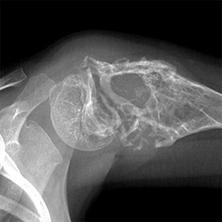

Течение опухоли, как правило, бессимптомное. Если наблюдается разрушение кортикальной пластинки, пациент может испытывать легкую болезненность при пальпации и визуальную деформацию челюсти. Рентгенограммами выявляется округлая форма деструкции костной ткани с четкими границами, что следует из чередования участков разрежения и уплотнения из-за неравномерной минерализации, окруженных зоной просветления в виде капсулы. Образование зачастую связано с корнем зуба, который не завершил своего формирования, и периодонтальная щель в области опухоли обычно не определяется.

Рентгенография костей таза показала обширную, почти полную деструкцию крыла левой подвздошной кости, с сохранением по периметру смещенного костного отломка, который был смещен кнаружи на 1,32 см и имел серповидную форму. Также была выявлена деструкция левой боковой массы крестца с четко выраженной полукруглой наружной границей.

Настоящий остеопороз наблюдается в остатках крыла левой подвздошной кости и верхней части вертлужной впадины. В мягких тканях кнаружи от левой подвздошной кости на рентгенографиях отмечается однородная тень, равномерная по форме, диаметром около 8 см, без признаков костных элементов (см. рис. 2). Заключение: миеломная болезнь.

Выявлена одиночная миелома (плазмоцитома) в левой подвздошной кости с распространением на крестец, осложненная переломом в нижней наружной 1/3 крыла. Дифференциальный диагноз: возможно остеобластома с остеопластическим типом?